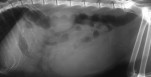

Les résultats globalisés montrent que le glucose interstitiel a eu tendance à monter la première semaine de traitement, puis à redescendre avec l'ajustement des doses, pour se stabiliser à partir de la semaine 4 (c'est-à-dire après la 3e injection).

À l'issue de l'expérimentation, les concentrations médianes en glucose ne sont pas différentes des valeurs de base (voir figure en illustration principale pour l'un des chats).